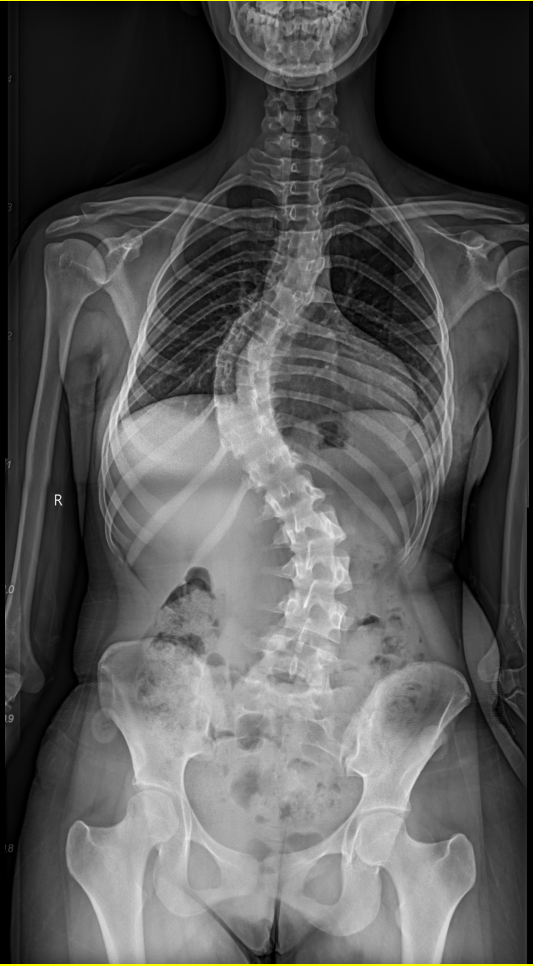

患者入院后,科室立即启动针对外籍患者的规范化诊疗流程,在语言沟通、检查安排、病情评估及围术期管理等方面进行系统协调。影像学检查显示,患者胸椎主弯 Cobb 角接近70°,伴明显椎体旋转,属于重度脊柱侧弯。该类患者手术涉及多节段矫形、脊髓安全保护及整体力学重建,对团队经验与协作能力要求极高。在骨科中心李浩鹏主任以及脊柱与骨肿瘤病区王栋主任、蔡璇副主任的统筹下,医院组织脊柱外科、麻醉科、影像科、神经电生理监测及护理团队开展多学科会诊(MDT),围绕手术策略、神经安全、失血控制及术后康复等关键环节,为外籍患者制定个体化治疗方案。与此同时,为保障患者顺利完成治疗,护士长李珂、陈静提前部署护理方案,安排专人全程负责护理工作,并指派英语沟通顺畅的陪护人员协助患者完成各项检查及术后护理,有效解决了语言与文化差异带来的就医障碍。

手术由脊柱与骨肿瘤病区副主任蔡璇教授主刀,李宇欢、王杰主治医师及刘璇规培医师协助,在全麻下实施后路多节段截骨矫形、植骨融合及内固定术。手术过程中需在大幅度矫正畸形的同时,严格防控脊髓神经损伤风险。神经电生理监测团队黄亚娟、孙丽君医师全程实时监测神经传导功能,为手术安全提供关键保障。在麻醉医师李路盼和手术室彭维、张宇坤主管护师的熟练配合下,历时6小时,手术顺利完成,术中出血量约600ml,未发生神经损伤等严重并发症。术后影像学评估显示,胸椎主弯矫形率超过90%,脊柱整体序列显著改善。术后,患者在多学科团队的协同管理下恢复良好,双下肢感觉及运动功能正常,身高增加7cm 以上。护理团队结合外籍患者需求,提供细致的围术期护理与康复指导,帮助患者顺利过渡至日常生活与学习状态。出院前,患者用英语向医护人员表达感谢:“Thank you for giving me a new life.”这不仅是对治疗效果的肯定,也体现了患者及家属对中国医疗技术与服务体系的高度认可。

图1 患者侧弯严重 背部畸形明显